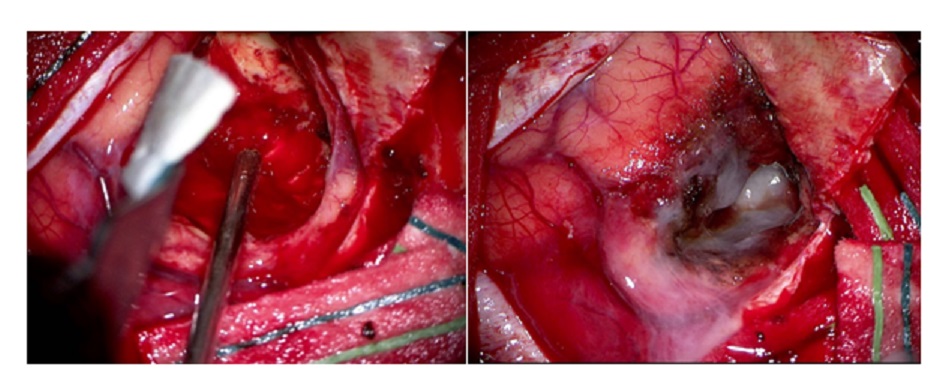

The gyrus overlying the tumour was obviously widened and broad. Aspiration yielded a haemorrhagic fluid. The tumour was encapsulated and could be delivered as a whole. But there was an area on the posterior superior aspect which was greyish red with sheaves of blood vessels coursing through it which still could be Glioma.

Dr. Houda provided excellent anaesthesia with a lax brain. I packed the tumour cavity with cotton balls to show that only the brain tumour was excised. Not a single millimetre of the normal cortex was touched. She recovered well and the right hemiparesis resolved within hours of surgery. Thanks to the ICU Team of Drs. Anas and Khamis; for close monitoring of the case preoperatively and postoperatively. These cases are tricky with a proclivity for sudden loss of consciousness due to hemorrhage in the Cystic tumour.